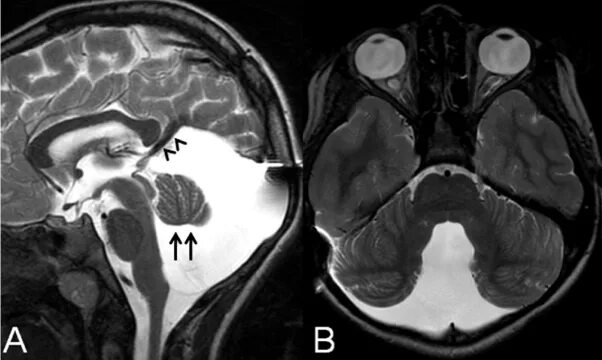

Денди уокера мрт